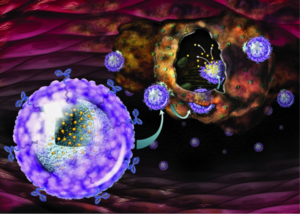

في 17 يناير 2019، اكتشف علماء من جامعة تورين للتكنولوجيا تقنية جديدة تستخدم الجسيمات النانوية الكهربائية للقضاء على الخلايا السرطانية.

حسب علماء من جامعة تورين للتكنولوجيا، من الممكن للجسيمات النانوية بعد ضغطها بالموجات فوق الصوتية، في تقنية تسمى التقنية الكهروضغطية، أن تطلق شحنات كهربائية لمهاجمة الخلايا السرطانية والقضاء عليها. كما طور الفريق آلية هامة للاستهداف، فالجزيئات النانوية يجب أن تُصمم بحيث تلتصق بالخلايا المسرطنة مع تجاهلها للخلايا السليمة، وقد أنجز فريق جامعة تورين للتكنولوجيا هذه المهمة عن طريق تغليف جسيمات النانو بپوليمر لدن، ثم وضع هذا المركب داخل أجسام مضادة تلتصق بمستقبلات موجودة في نوع بعينة من الخلايا السرطانية.[14]

أجرى الفريق تجاربهم على أحد أشرس أنواع سرطان المخ، المسمى بالورم الأرومي الدبقي متعدد الأشكال glioblastoma multiforme، وفي أغشية مستقبلات التراسنفيرين، على النقيض من أغلب الخلايا السليمة، لذا، قام العلماء بتغليف جزيئات النانو بغشاء من أجسام الترانسفيريني المضادة، التي تلتصق بمستقبلات الترانسفيرين على الخلايا المسرطنة، ويؤدي هذا إلى تحويل الجزيئات النانوية إلى ما يشبه الصواريخ الموجهة التي لا تستهدف إلا الخلايا السرطانية، ويجب أن تمر الجزئيات النانوية أيضاً عبر عائق خلايا دم المخ، وهو عامل مهم في علاج سرطان المخ، يمكن للجزيئات النانوية إنجاز هذا الأمر إذا كانت بصغيرة بالقدر الكافي، لذا إختار الفريق جزيئات يبلغ نصف قطرها 300 نانو-متر، وهو الحجم القادر على تجاوز هذا العائق.